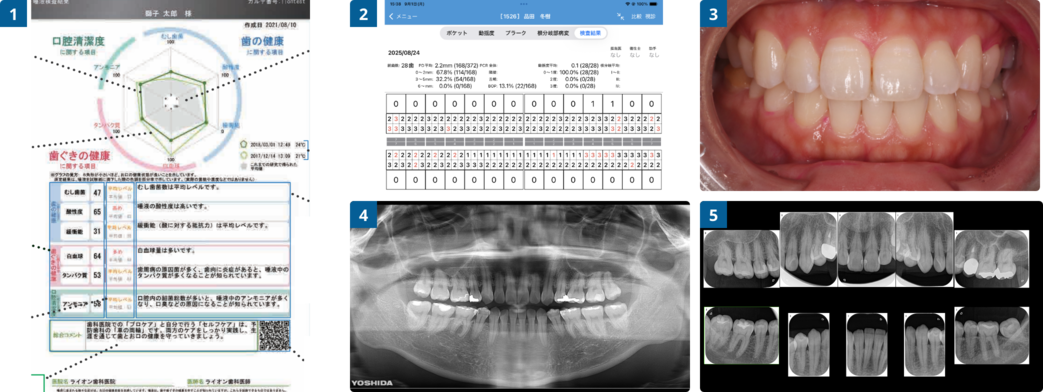

1問診・診査

問診を通じて、日頃の食べ物の嗜好や喫煙の有無を事前に知ることで、患者様自身の歯周病や虫歯のリスクを把握します。また、行う検査は現状の有病箇所を早期発見するのとともに、今後の記録として採取します。細かい記録を常にとることで、少しの変化でも的確に診断する助けとなります。初診および1年ごとに詳しい検査を推奨しています(定期検診)

1唾液検査

1唾液検査5分程度でできる簡易的な唾液検査を行うことで、患者様の唾液の質をお調べします。虫歯菌(虫歯リスク)、酸性度(虫歯のなりやすさ)、緩衝能(虫歯のなりにくさ)、白血球(炎症の有無)、タンパク質(磨き残し)、アンモニア(口臭)の6つの項目をお調べすることによって現状の虫歯リスクや歯周病のリスクを相対的に判断することに役立てます。

2歯周ポケット検査通常の歯周ポケットは2mm~3mmです。それ以上は病的な状態です。また、検査中の出血は歯茎が弱まっていることを意味してとり、炎症があることが疑われます。

定期的に歯周ポケット検査を行うことで、歯肉炎や歯周病の増悪を確認し、歯茎の健康状態を把握します。3口腔内写真定期的な口腔内写真の記録をとることで、お口の中のトラブルが発生したとき何が原因だったかという過去の情報を確認することができます。また、染め出し後に磨き残しをご自身で確認していただくためにも活用します。

4パノラマX線写真全体的なレントゲン写真をとることで、全体的な骨のレベルや歯のスクリーニング検査を行います。(初回・その後隔年)

5デジタルX線写真(10枚法)小さいレントゲンを撮影することで、歯周組織や虫歯の有無、根の病気の発見を行います。(初回・その後隔年)